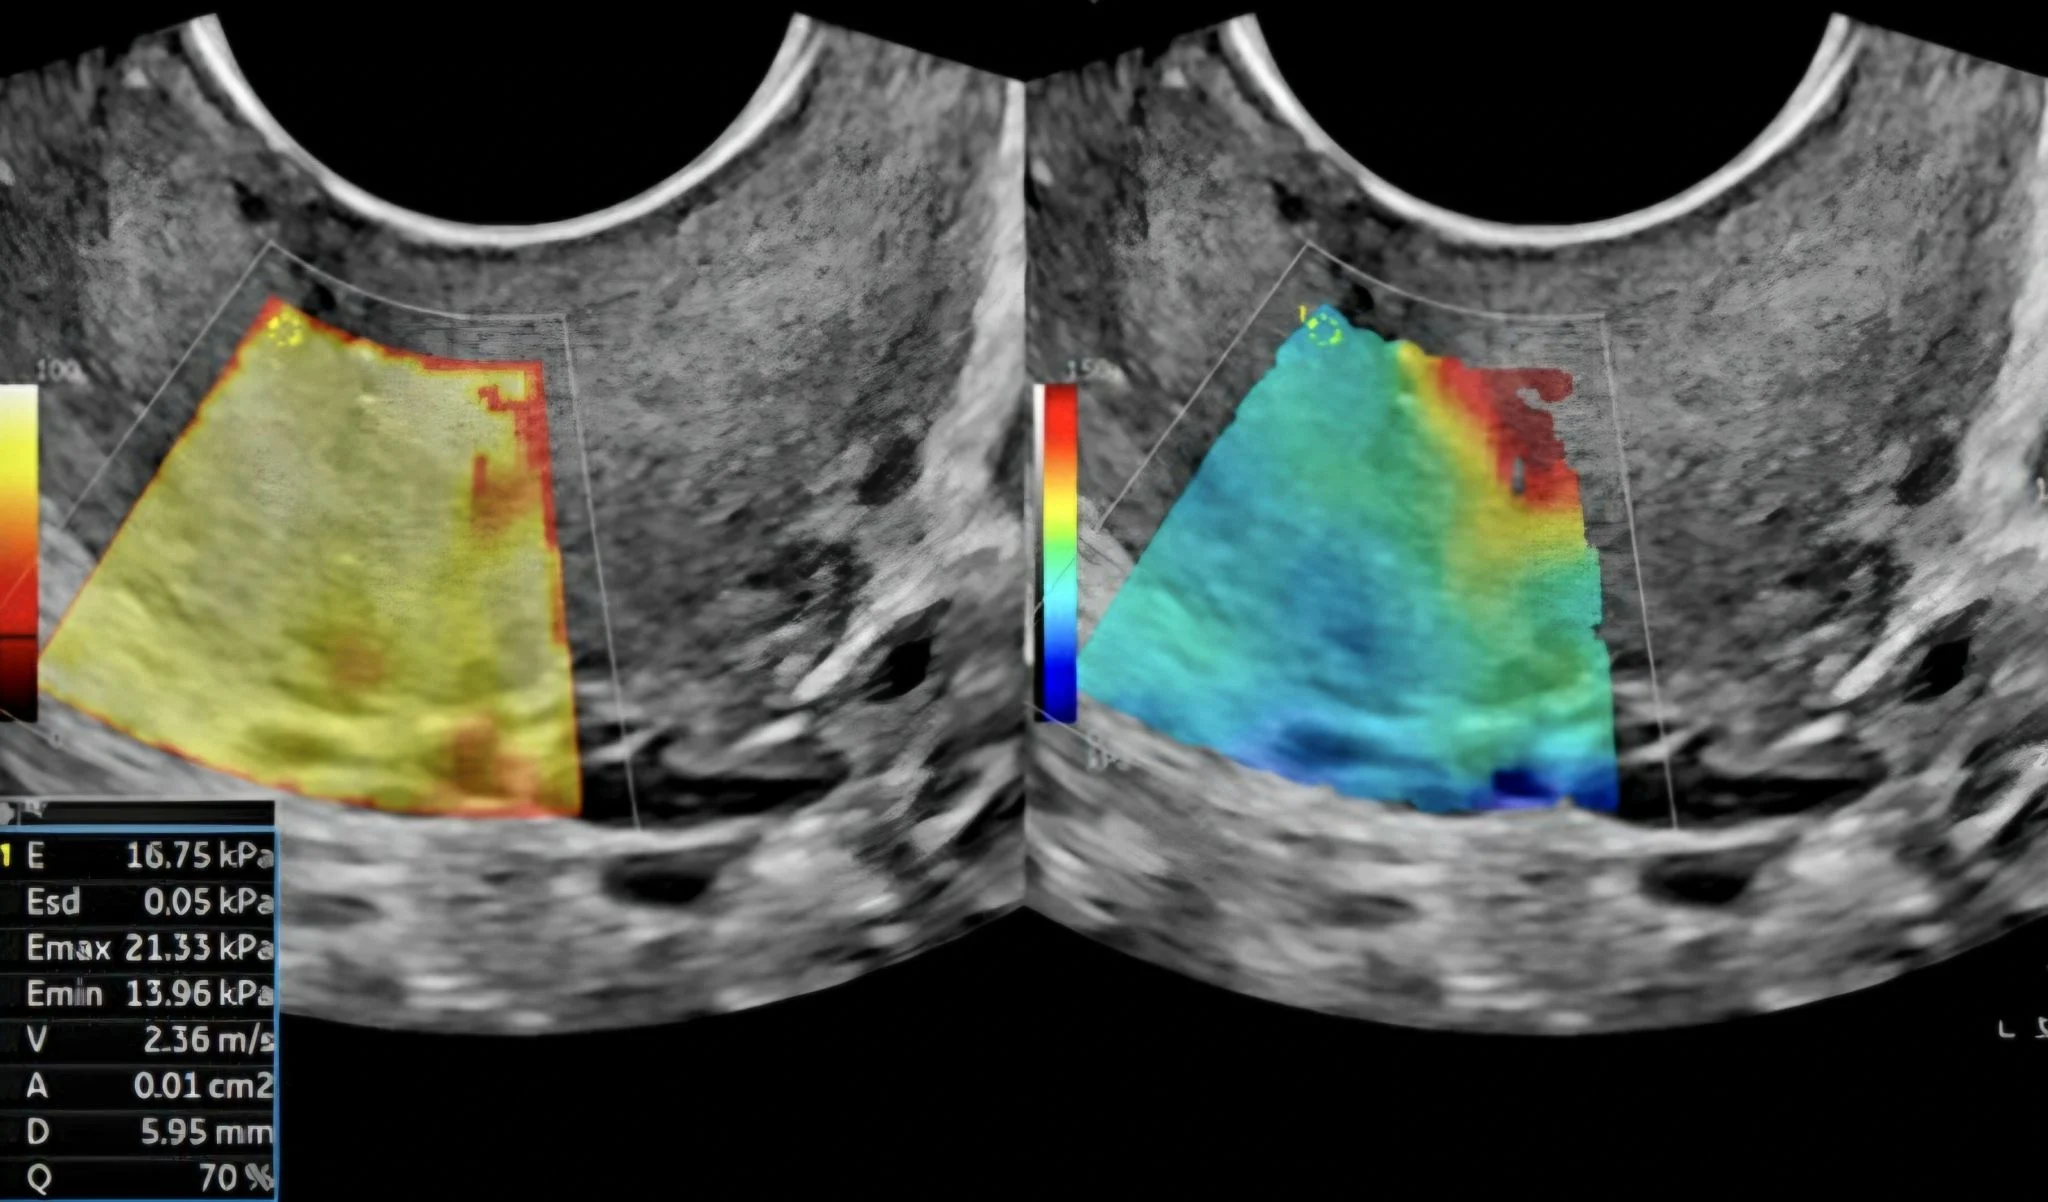

A very recent study conducted by Ufuk Üniversitesi in Ankara and Etilik City Hospital examines elastosonographic parameters in six different zones:

SWE (Shear-Wear Elastography) showed higher stiffness measurements for the anterior and posterior internal os compared with the controls.

The stiffness of the internal cervical os (ICO) appears to be the most significant parameter, and women with adenomyosis have a significantly stiffer internal os than those without the condition

Cervical elastography may serve as a non-invasive adjunctive tool for exploring disease-related biomechanical changes